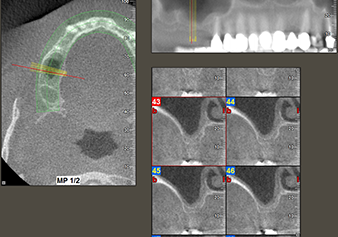

Fig.2: The DVT shows adequate dimensions in each of the axial (left), lateral (top) and transverse views (right). The maxillary sinus membrane is still slightly thickened.